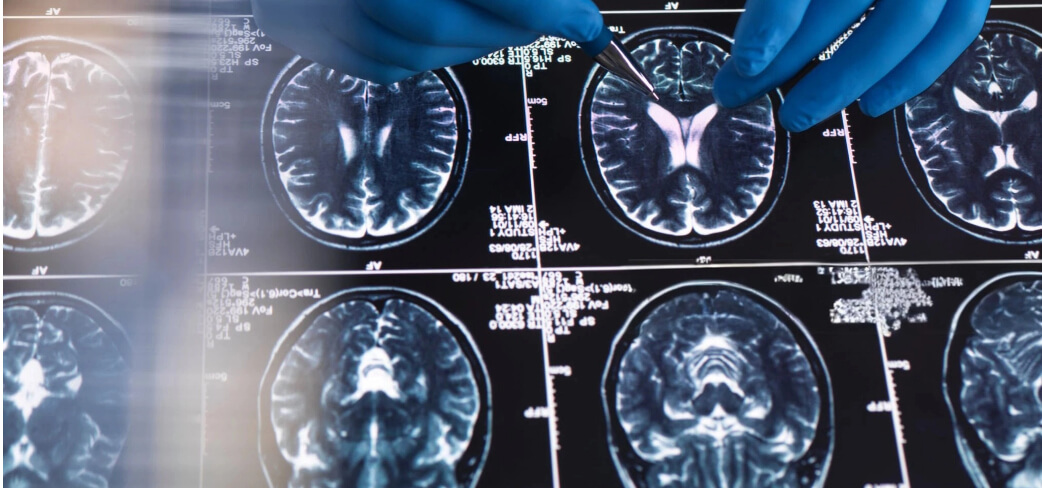

The new study followed three patients undergoing hand amputation, using functional MRI scans taken before and after surgery. Participants were asked to move their fingers or purse their lips while in the scanner, allowing researchers to observe the corresponding brain activity. Results revealed remarkable stability: even months or years after amputation, the brain regions linked to the missing hand were still activated almost as if the hand were still there.